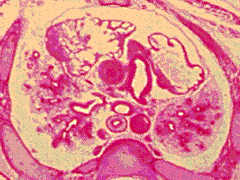

Dl:

Sternum. Thymus. Lungs. Visceral and parietal

pleurae. Pleural cavities. Other contents of

superior mediastinum.